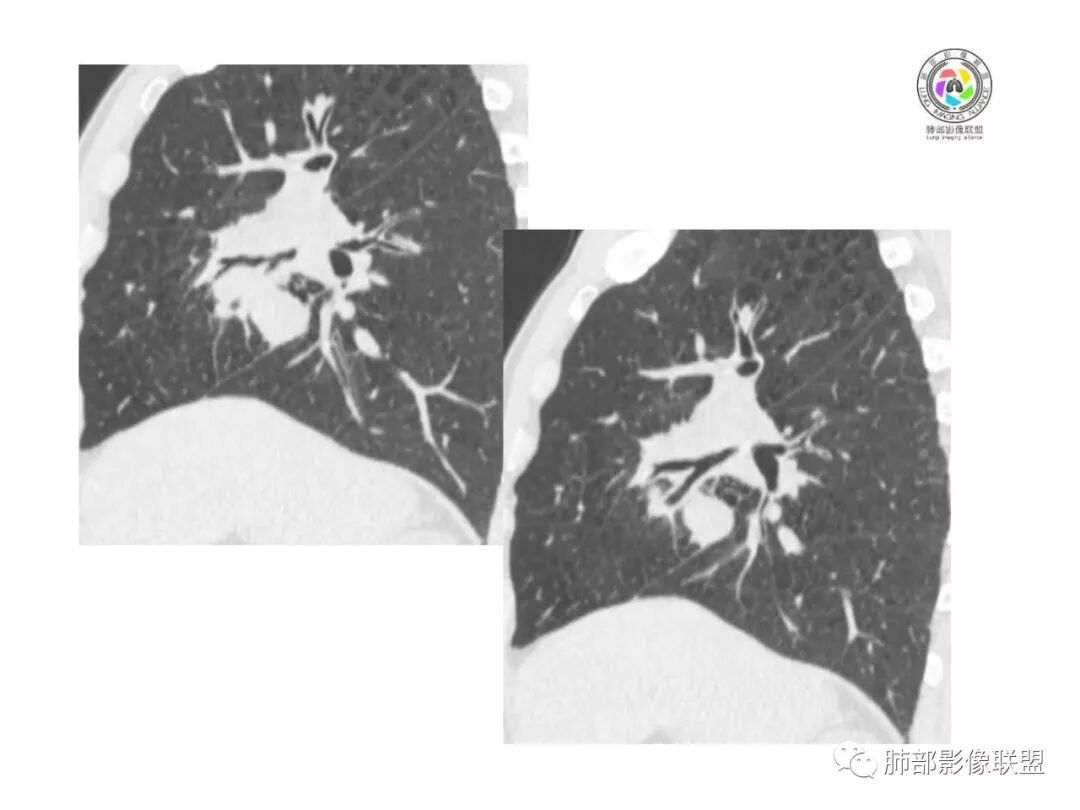

找一下支气管,

上叶支气管没有找到,是没有给还是真的堵了

支气管有阻塞有推挤

中叶支气管还再,推移加堵塞,但是推移为主,我觉得肯定不是中叶的中央起源

下叶也都在

我现在想知道上叶支气管是全部堵了还是没有给都图片。如是没有堵塞,就是外向内的腺癌或间叶来源,如果上叶堵了,就不一样

因为中叶和下叶支气管没有堵塞为主,是外向内的迹象,现在我就是上叶图片的问题

我也是看到支气管似乎没有堵塞,除外鳞癌

堵塞得不适外侧段,是内侧段

@吴婧南京市第一医院 这个从影像表现,坏死情况,以及叶裂推移情况与支气管推移情况来看,还是支持中叶间质来源,外朝内生长,同时向上,向下,向内都有推移作用。

病灶大,支气管受压、堵塞——提示外围来源,恶性

这个支气管也是有移位的感觉

两个支气管都是移位

这个血管在病灶中间走行。鳞癌不会这样的。

2.肿块巨大局部边缘膨隆、光整,坏死较彻底;明显跨叶生长(途经发育不全叶间裂或肺门,注意患者没有胸水),支气管阻塞伴推移等,这些更符合肉瘤的特性。

3.坏死区边界较清楚(皮囊样),环形强化明显,病灶内血管穿行等,都不符合我们常见的鳞癌。